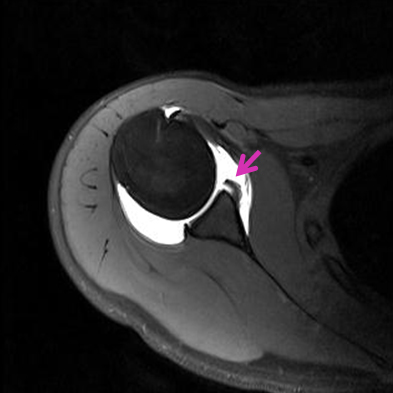

MRI 사진에서는 파열된 전방 관절순을 관찰 MRI 사진에서는 파열된 전방 관절순을 보입니다

급성 탈구인 경우 진찰소견과 엑스레이 소견을 보고 탈구의 방향을 조사하는데 대부분의 경우 팔이 앞쪽으로 빠지는 전방 탈구입니다. 재발성 탈구가 되면 MRI 등으로 관절순 또는 인대들의 상태를 분석하는 것이 필요합니다. 또한 재발성 탈구시 골절을 동반하는 경우와 골결손이 심하면 수술전 CT사진이 필요합니다.